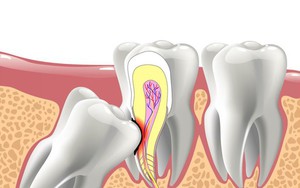

răng khôn

Răng khôn mà… không khôn

Về mặt sinh lý học, răng là công cụ để cắt xén thức ăn cho dễ tiêu hóa.

Vì sao luôn mọc ở chỗ không ai muốn, gây đau đớn nhưng răng khôn lại được đặt cái tên “thông minh” như vậy? Đáp án thật ra rất hợp lý

Dù là trong tiếng Việt, tiếng Anh hay nhiều ngôn ngữ khác, những chiếc răng thừa gây khó chịu này đều có tên là răng khôn.